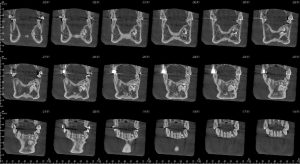

طلب منى اشعة بانوراما عادية علي الفكين و عملتها و تم عرضها علية فعاد و طلب مقطعية للتأكد من شيء موجود تحت الناب الايسر بالفك السفلي و بالفعل عملت المقطعية وتم عرضها علية

وقالي هنتابعها هى حاجة عندك من سنين طويلة يمكن اكتر من ٢٠ سنة و موجودة في اشعات البانوراما القديمة اللي كنت بتعرضها علي دكتور شريف المفتي في ٢٠١١ و ٢٠١٢ رحمة الله علية هى اسمها compound odontoma و حاجة حميدة تماما و لا خوف منها و ممكن تعيش بيها لكن هنتابع حجمها بالمقطعية كل ٦ شهور و متقلقش منها .

قولت اعمل اشعة بانوراما مع نفسي كدا اطمن علي المشكلة.. لقيت الحجم شكلو متغير عن اللي فاتو بتوع ٢٠١٨ و ٢٠١١

و٢٠١٢ بعتها لدكتور محمد المفتي واتس واتصلت علية .. قالي مالك مال صوتك مخنوق !

قولتلة انا ملاحظ تغيير قالي نعمل مقطعية قولتلة فين قالي مضطر تنزل القاهرة كدا

قولتلة طبعا قالي انا هكون موجود هناك غدا بكلية طب الأسنان تعالي و هنعمل مقطعية عندنا و بالفعل روحت قالي اسمع البانوراما دى بايظة و مش هيطلع اي تغير قولتلو لا يا دكتور انا ملاحظ الاشعة و الفرق قالي ماشي يا فندم بينا المقطعية!

و من قلقي كل شوية اتصل علية و الراجل يرد و يشرح و يشرح و انا منتظر المقطعية لحد ما عملت المقطعية من يومين و تركت ال cd للدكتور محمد المفتي لان وجدته في اجتماع مع رئيس جامعة النهضة بني سويف

و بعد عرض ال cd قومت بالاتصال علية قالي مافيش اي تغير يا نادر زى ماهي و مافيش حاجة تخوفني.